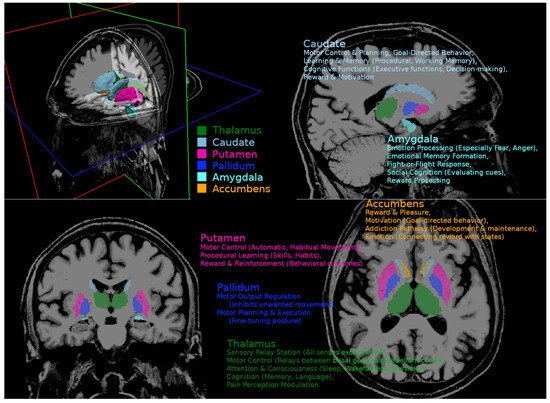

Our analysis focused on the deep gray matter regions, as elevated iron levels have previously been found in these areas in cirrhotic patients. We did not assess susceptibility changes in white matter because the counteracting effects of myelin and its orientational dependency hinder clear interpretation. Several methods have been proposed for segmentation of the basal ganglia and thalamus. We employed the multimodal segmentation technique MIST to improve the robustness of the segmentations [22]. MIST combines T1 and T2 contrast and fractional anisotropy (FA) maps to model intensity profiles in multiple images around the boundaries of the structure after nonlinear registration. The advantage of this approach is more robust segmentation, especially in regions where T1 contrast is low. FA maps were calculated from DWI data using the TORTOISE tools [23]. The TORTOISE tool “diff_prep” was applied, using quadratic eddy current correction, ANTSSyN EPI distortion correction, and noise reduction for registration and Gibbs ringing correction. DTI-related metrics, including MD, RD, and FA, were calculated using the tool “diff_calc” from TORTOISE. We focused on subcortical structures involved in cognition, emotion, and motor function, including the globus pallidus, amygdala, CNA, putamen, and thalamus. Graphical presentation of observed regions and their functional involvement is presented in Appendix A. The mean susceptibility of each region of interest (ROI) was calculated using AFNI’s “3dROIstats” program and averaged for both hemispheres [24].

Figure A1. Functional neuroanatomy of the basal ganglia and related nuclei.